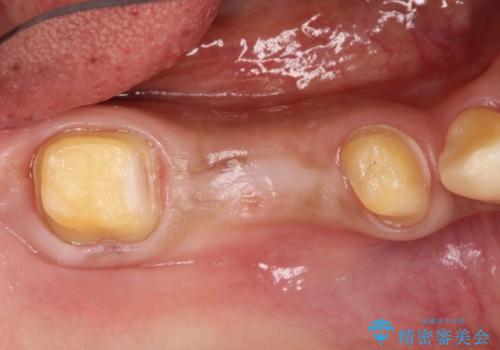

- 奥歯が痛いことを主訴に来院されました。

遠心根に歯根破折を認め、保存不可と判断しブリッジにて欠損補綴を行なっております。